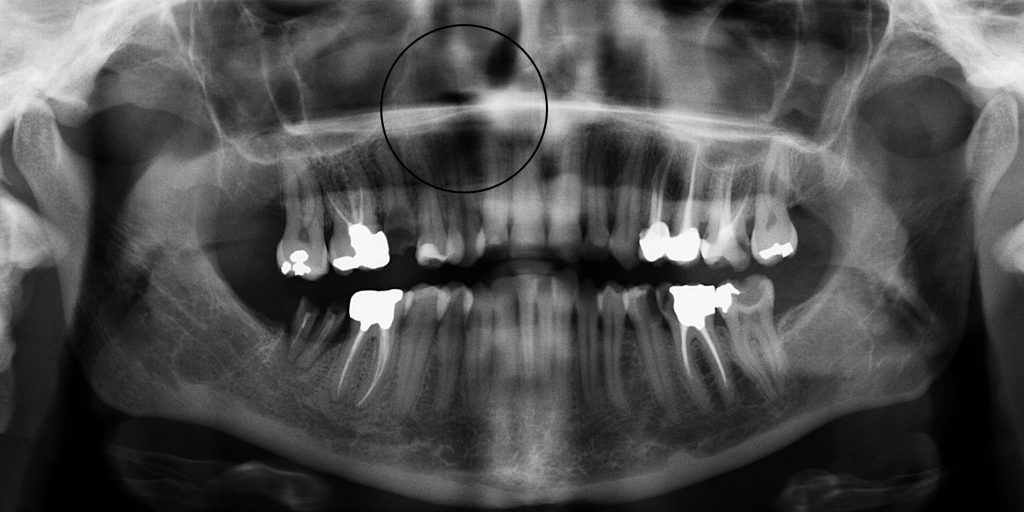

- Radiografia endorale: permette di visualizzare l’area intorno all’apice e verificare la presenza di lesioni.

Cisti radicolari: piccole cavità piene di liquido che si sviluppano vicino alla radice del dente

Granuloma apicale: infiammazione cronica con tessuto di difesa che si forma attorno all’apice